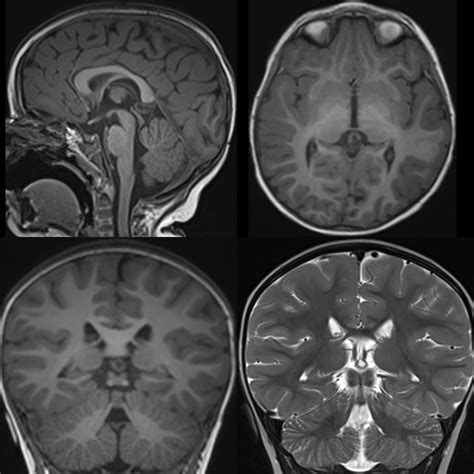

Magnetic Resonance Imaging (MRI) The gold standard for visualizing the size, characteristics, and location of the cyst.

In cases where the cyst is small (usually less than 1cm) and the patient is asymptomatic, the standard protocol is "watchful waiting." This involves periodic follow-up MRI scans to ensure the cyst is not growing. Because most pineal cysts do not grow, many patients require only one or two follow-up scans before being cleared from routine monitoring.